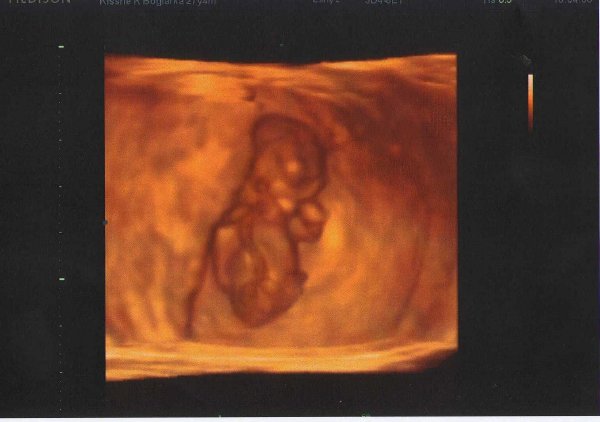

Beni 30 hetesen:

Kép